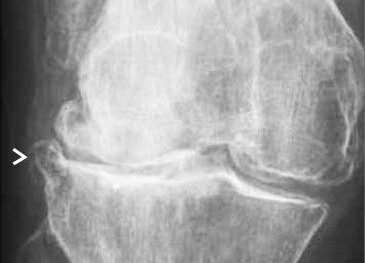

The management of chondral disease poses challenges due to its poor healing potential. Biomechanical and biological changes can accelerate degeneration, leading to end-stage osteoarthritis (OA).

The study, approved by the Ethics Committee, involved 30 patients with diffuse degenerative chondral lesions treated with autologous micro-fragmented adipose tissue between January and December 2014. Clinical evaluations were conducted at 3 years post-treatment.

Patients not requiring additional treatments maintained outcomes observed at 1 year, with significant improvements in functional scores including Tegner Lysholm Knee, VAS pain, IKDC subjective, and total KOOS.

The study demonstrates sustained benefits of autologous micro-fragmented adipose tissue in treating diffuse degenerative knee chondral lesions at mid-term follow-up, supporting its role as an adjunct in surgical procedures.